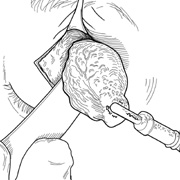

Many deep orbital lesions requiring removal of the lateral orbital rim can be approached through a smaller lateral canthotomy incision. Although Berke17 initially described a fairly extensive lateral canthal incision extending back over the zygomatic arch for 5 to 7 cm, this longer incision often leaves an unsightly scar and may risk damage to the seventh cranial nerve. Because of the extensibility of the periocular tissues, exposure of the lateral orbital rim usually can be accomplished through a small lateral canthotomy incision measuring 1 to 1.5 cm in length (Figs. 10, 11, and 12). With wide undermining in the suborbicularis plane and retraction of the skin and orbicularis, superior and inferior osteotomies can be made quite readily despite the small external incision. The incision always can be extended farther posteriorly if exposure is inadequate.

Figure 10. A. Large, well-encapsulated intraconal mass on MR scan. B. Small lateral canthotomy incision will be used to perform lateral orbitotomy and remove the intraconal mass.

Fig. 11. A. Lateral canthotomy incision is made with straight iris scissors. B. Periosteum is elevated off of the lateral orbital rim. C. Wide undermining allows retraction of the skin incision to permit superior and inferior osteotomies to be made with the air-driven saw. D. The bony rim has been outfractured. Because of the distensibility of the skin, it is possible to remove a large bone flap through the small canthotomy incision. E. The intraconal mass is extracted with the aid of the cryoprobe. F. The bone fragment is positioned for resuturing.

Fig. 12. A. The lateral canthotomy incision is reapproximated with simple closure of the superior and inferior crura of the lateral canthal tendon. A drain from the temporal fossa has been brought out through a separate stab incision posteriorly. 12B. Excellent postoperative scar camouflage is obtained by this approach.